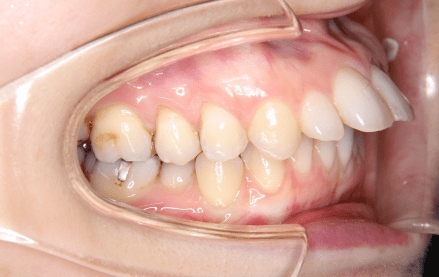

上顎前突は、いわゆる出っ歯の状態で奥歯をかみ合わせた状態で、上下の前歯が離れて前後的な隙間がある状態のことを指します。

マウスピース矯正で上顎前突(出っ歯)を治療することができます

当院では、上顎前突(出っ歯)の矯正治療も全てマウスピース型矯正装置にて行っております。下記ボタンから、実際の症例をご確認いただけますので是非ご確認ください。